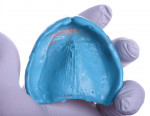

In the first step in this digital workflow, the patient's existing dentures are used as custom trays to make definitive impressions of both arches. For the mandibular definitive impression, a medium body regular set impression material (Aquasil®, Dentsply Sirona) was used (Figure 4). This high viscosity medium body material was chosen for the mandibular impression in order to best capture the lingual flanges. For the maxillary definitive impression, a light body impression material (Aquasil®, Dentsply Sirona) was used (Figure 5). This material was less viscous than the medium body impression material, which helped to completely seat the maxillary denture.